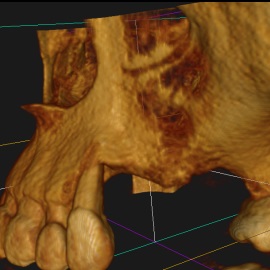

Pacjent z długą historią leczenia implantologicznego. Pierwsze implanty w pozycjach 23, 24 miał wkręcane w Warszawie przed 25 laty. Implant w pozycji górnego prawego kła ma agresywny gwint, ponieważ bezpośrednio po implantacji był obciążony (immediate loading) tymczasowym atachmentem ball abutmentv do stabilizacji tymczasowej protezy ruchomej. Kość szczęki regenerowana i odbudowywana etapami w całym górnym prawym kwadrancie. Pacjent planuje uzupełnić brakujące zęby 25, 26.